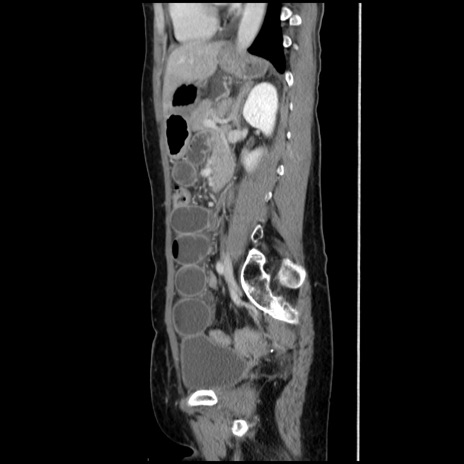

横断像

【症例】40歳代 女性

【主訴】上腹部痛、嘔気・嘔吐

【現病歴】約9時間前頃から急に上腹部痛、嘔気、嘔吐が出現。改善しないため救急要請。

【既往歴】子宮頚癌(広汎子宮全摘術、放射線療法)、腸閉塞

【身体所見】腹部:平坦、軟、腸雑音亢進、上腹部を中心に腹部全体に圧痛あり。

【データ】WBC 8400、CRP 0.03